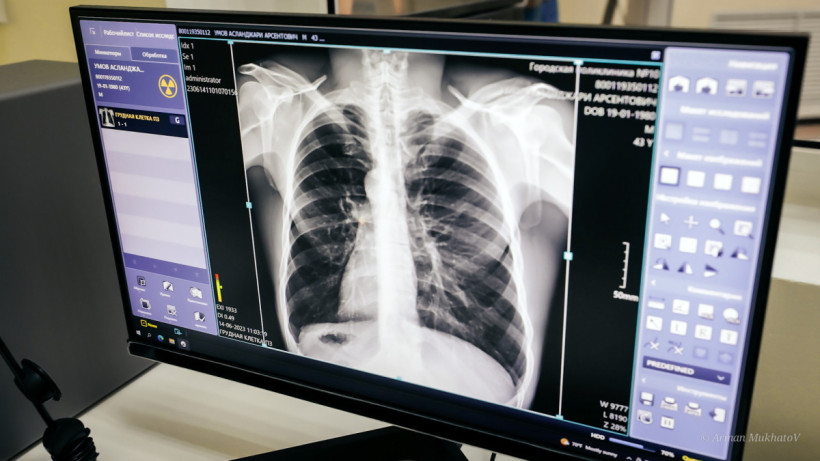

Қазақстанда туберкулезбен сырқаттану көрсеткіші екі есе төмендеді

©El.kz/Арман МҰХАТОВ

Фото: ©El.kz/Арман МҰХАТОВ